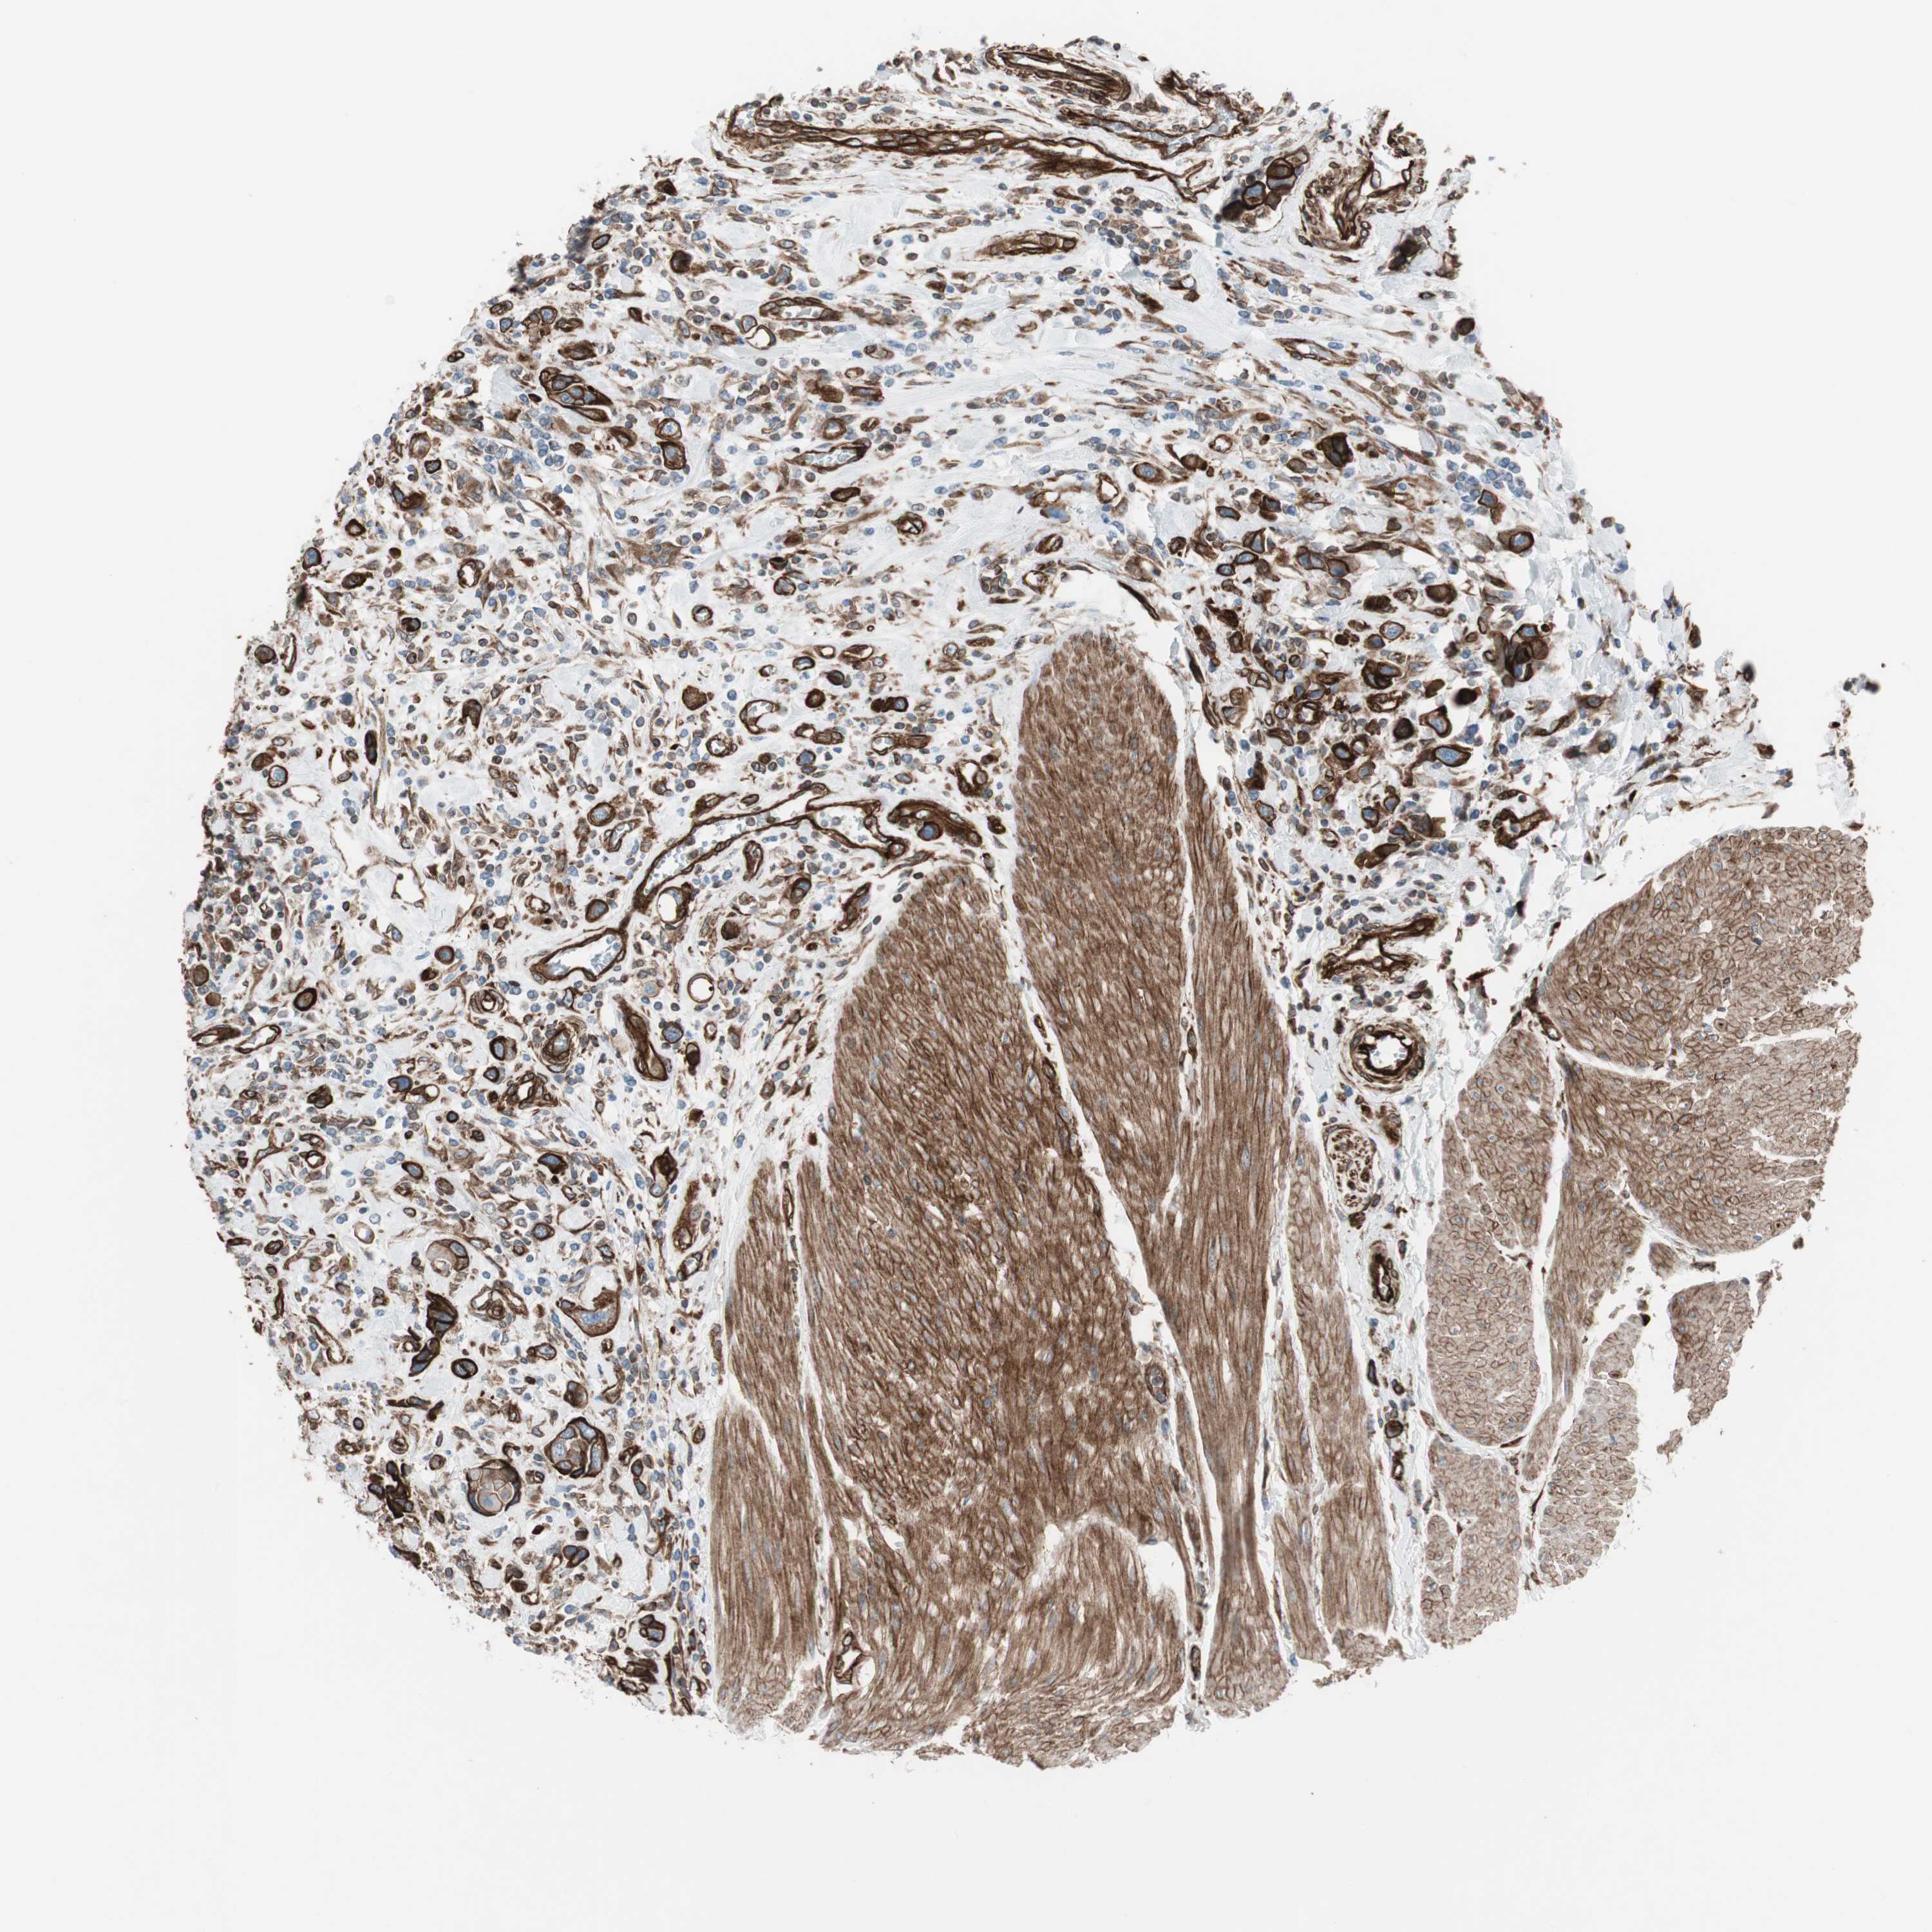

UROTHELIAL CANCER - Protein expressioni

A mouse-over function shows sample information and annotation data. Click on an image to view it in a full screen mode. Samples can be filtered based on level of antibody staining by selecting one or several of the following categories: high, medium, low and not detected. The assay and annotation is described here.

Note that samples used for immunohistochemistry by the Human Protein Atlas do not correspond to samples in the TCGA dataset.

Antibody stainingi

Antibody staining in the annotated cell types in the current human tissue is reported as not detected, low, medium, or high, based on conventional immunohistochemistry profiling in selected tissues. This score is based on the combination of the staining intensity and fraction of stained cells.

Each image is clickable and will lead to virtual microscopy that enables deeper exploration of all samples and also displays staining intensity scores, fraction scores and subcellular localization as well as patient and tissue information for each sample.

Antibody HPA007342

Staining

High

Medium

Low

Not detected

Intensity

Strong

Moderate

Weak

Negative

Quantity

>75%

75%-25%

<25%

None

Location

Nuclear

Cytoplasmic/membranous

Cytoplasmic/membranous,nuclear

Urothelial carcinoma, High grade

Urothelial carcinoma, Low grade